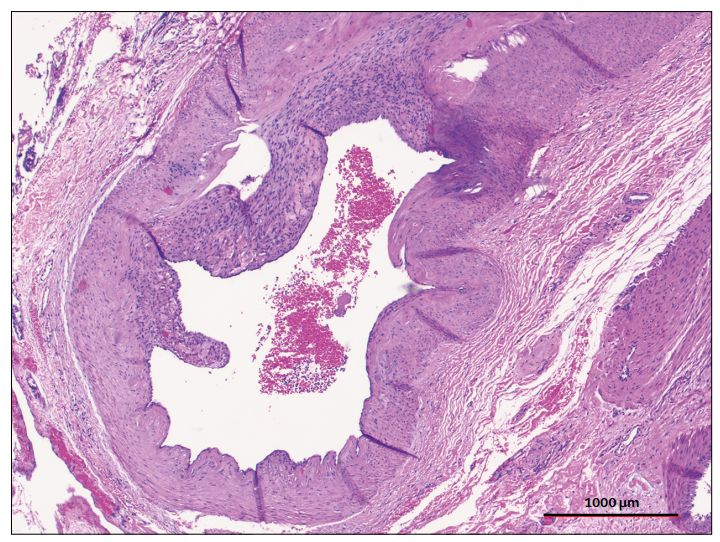

图5:子宫动脉伴轻度内膜纤维增生,无钙化、炎症。子宫动脉的苏木精和伊红(H&E)染色。